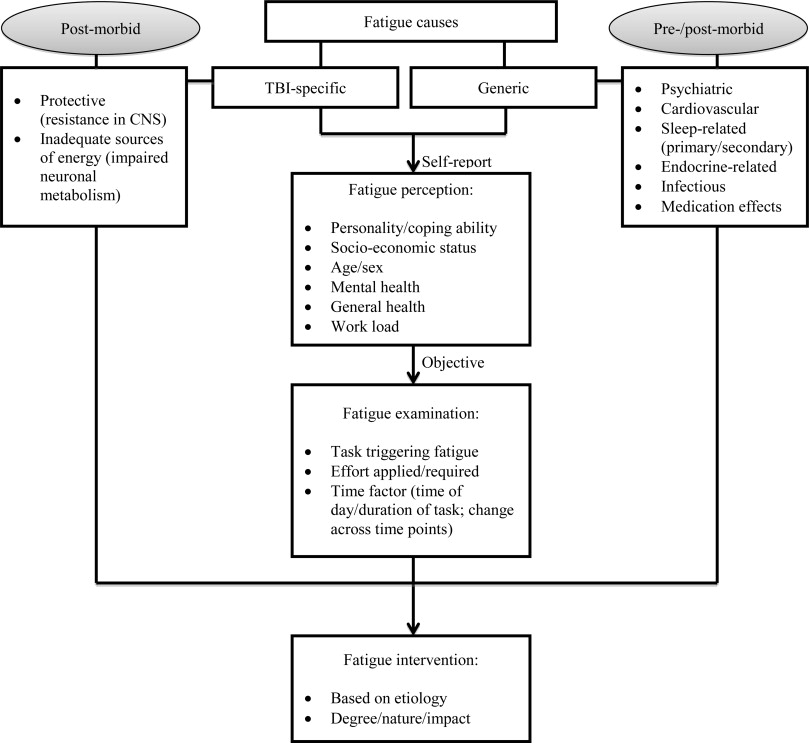

7e) Neurological Effects of Apnea

Excessive daytime sleepiness (EDS) in OSA is associated with significant changes to the brain

Obstructive sleep apnea (OSA) is associated with reduced gray matter concentration"

Imaging studies in patients with severe OSA showed reduced gray matter concentration in certain brain regions compared with healthy volunteers, including the frontal cortex, anterior cingulate cortex, and thalamus.''

Some of these regions are involved in wakefulness and neurocognitive performance in' • Problem-solving • Planning • Decision-making • Attention/concentration

EDS in OSA is associated with significant white matter structural alterations despite the optimal use of CPAP'

Widespread white matter changes were observed in patients with OSA-associated EDS despite optimal CPAP adherence hours for 1 month) vs nonsleepy patients'

These changes ideate potential myelin damage and compromised neuronal connectivity'

This may help explain why EDS can persist in patients with OSA, even with optimal CPAP use?

Excessive daytime sleepiness (EDS) in OSA is more common than you may think

- Animal and human studies indicate a link between obstructive sleep apnea (OSA) and changes to the brain—and these changes have been associated with a disruption in neurologic function'

- While CPAP is needed to address the airway issue in patients with OSA, it may not address all aspects of compromised neuronal activity, and EDS may persist"